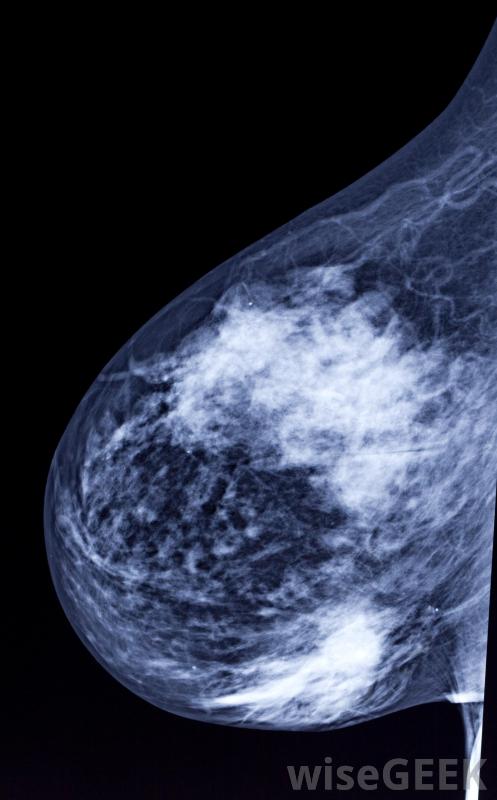

什么是數字乳房X光片(Digital Mammogram)?

數字乳房x光攝影使用傳統的x射線方法,但是乳房組織的圖像是用電子x光機拍攝的,它以數字格式存儲圖像。圖像在計算機屏幕上顯示,然后放射科醫生可以調整對比度,增強或放大x光片以顯示檢測結果。傳統的乳房x光片在膠片上生成圖像,放射科醫生和醫生通過將圖像置于光源上進行檢查由于膠片曝光不足或曝光過多,數字乳房X光片不再需要重復掃描。數字乳房X光片需要更少的時間來記錄圖像,以檢查是否存在異常乳房組織,從而減少與手術相關的疼痛。檢查要求將乳房放在一個平坦的表面上,在進行x光檢查時,有一個裝置壓迫乳房。乳房的組織需要展開,以允許機器觀察所有的組織,并防止組織堵塞異常在拍攝圖像時,女性必須保持非常安靜,避免呼吸,以防止x射線散射或無法讀取的掃描乳房組織很少有研究證實數字乳房X光攝影的好處,但是一些科學家和醫生已經展示了使用這項技術的有希望的結果,由于在乳腺組織成像過程中由于運動而導致掃描不可讀,重復的乳房X光片減少了。數字乳房X光片允許放射科醫生通過編輯技術改進測試圖像,從而產生更清晰的結果,更容易檢測腫塊或腫瘤樣結構。這種技術由于膠片曝光不足或曝光過多,也不再需要重復掃描。對于一些辦公室和患者來說,測試成本是一個問題,但由于數字乳房X光片是數字化存儲的,它降低了員工和存儲空間的開銷膠片。數字化篩查的完成速度要快得多,讓放射科醫生可以在一天內完成更多的乳房X光片檢查。在較短的手術過程中,女性受到的輻射較少,這可能有助于緩解一些患者的安全顧慮。數字成像技術的進步可能會給篩查中心帶來未來的好處,并且為病人提供更準確的結果。建議50歲以上的婦女每兩年進行一次乳房X光檢查。乳房X光檢查可以發現可能是乳腺癌征兆的腫瘤或腫塊。定期檢查建議醫生將之前的掃描結果與當前圖像進行比較,以確定是否有變化或增長。